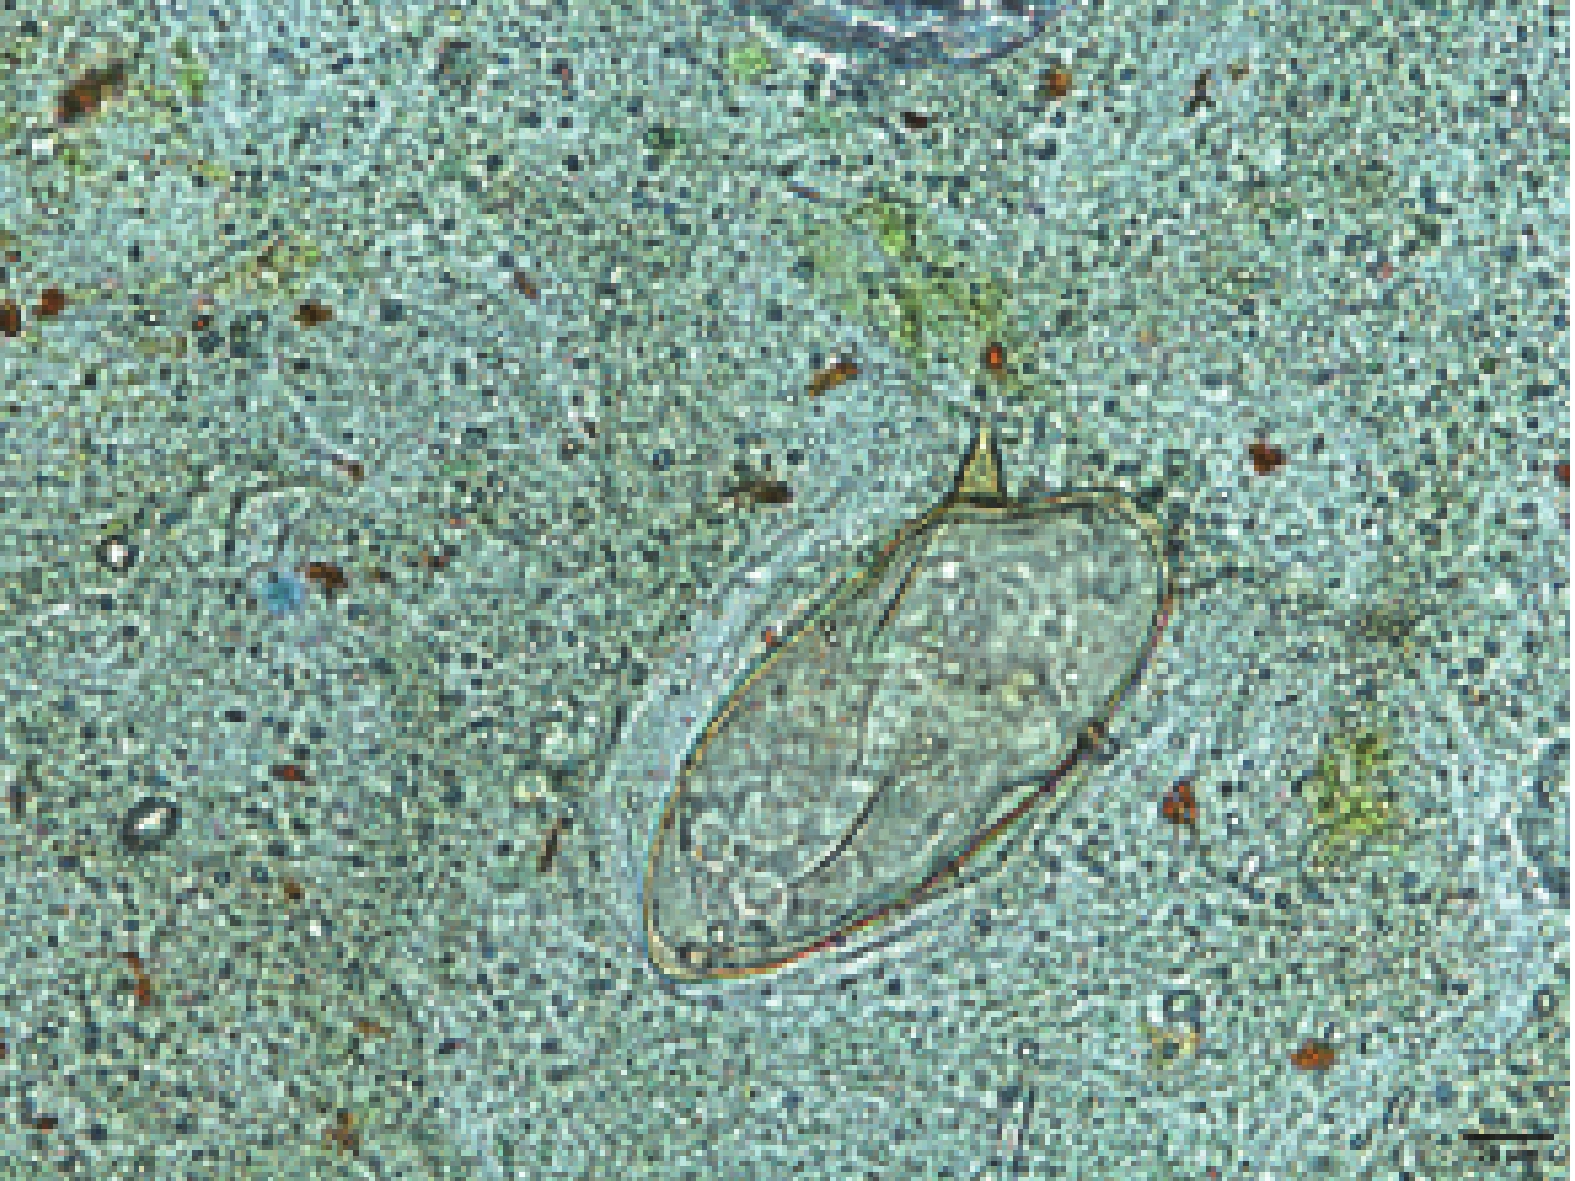

First Imported Case of Cerebral Schistosomiasis Mansoni — China, May 2025

Weiqi Chen, Yalan Zhang, Xiaohui Ma, Tiantian Jiang, Dongyang Zhao, Yan Deng

2026, 8(5): 131-134. doi: 10.46234/ccdcw2026.021

Schistosoma mansoni (S. mansoni) is predominantly distributed across Africa, the Middle East, the Caribbean Islands, and South America, infecting approximately 54 million people annually. China is not an endemic region for schistosomiasis mansoni, and no cases of cerebral schistosomiasis mansoni have been previously documented.

What is added by this report?

This report documents the first imported case of cerebral schistosomiasis mansoni in China. We present the epidemiological investigation, distinctive clinical manifestations, diagnostic challenges including misdiagnosis and delayed diagnosis, and the critical role of pathogen detection in case confirmation.